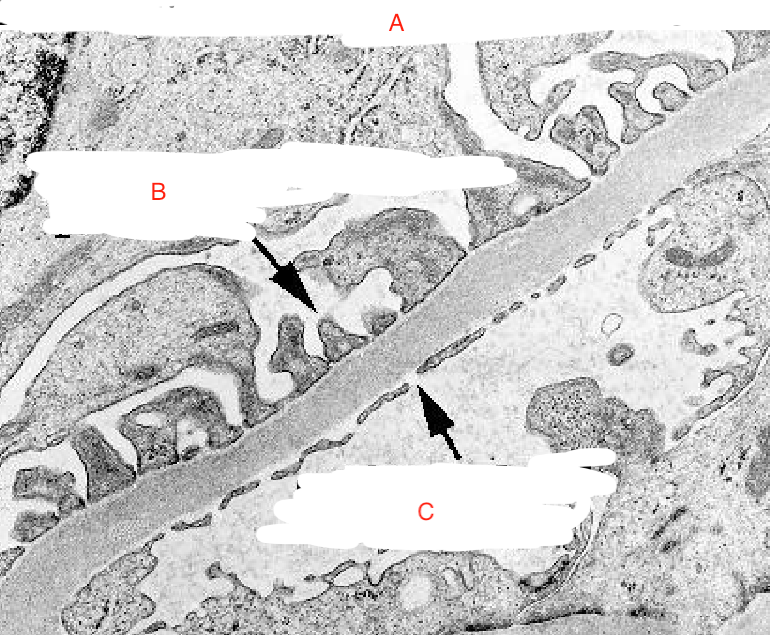

Glomerular Filtration Membrane

B

Endothelial Foot Process

C

Endothelial Cell Pore